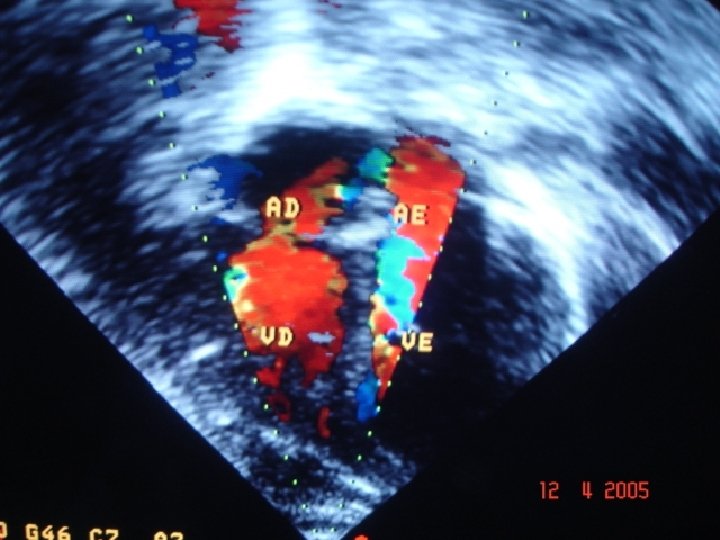

Evolução § Ecodoppler de carótida solicitado dia 06/04 § (investigação de tromboembolismo, vasculite e malformações vasculares). Resultado(11/04): normal Ecocardiograma solicitado dia 07/04 (investigação de cardiopatia). Resultado (11/04): Situs solitus, concordância AV e VA, câmaras cardíacas de dimensões normais, sem fluxos transvalvares. Não foram visualizadas vegetações, trombos ou aneurismas. Conclusão: normal.

Foto Ecocardio

Possíveis Etiologias • Essas afecções cardíacas foram descartadas pelos exames de ecocardiograma e pela pesquisa do hemograma (infecção).